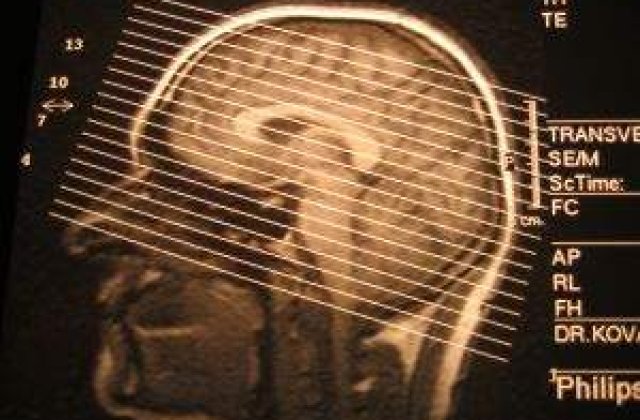

"Operatia este necesara pentru ca ar avea hidrocefalie, adica lichid in zona creierului. Medicii urmau sa scoata lichidul miercuri, insa, intrucat pacientul are infectie urinara, trebuie tratata mai intai aceasta suferinta", au precizat sursele citate de MEDIAFAX.

Actorul Iurie Darie, in varsta de 83 de ani, a fost adus la Spitalul de Urgenta "Bagdasar-Arseni" din Capitala in carucior, el neputand umbla. Dupa tratament, starea lui s-ar fi ameliorat.

"Acum, se misca, dar trebuie scos lichidul", au mai spus apropiati ai actorului.

Darie se afla in spital de saptamana trecuta, unde fusese adus pentru pentru investigatii medicale de rutina, dupa cum a declarat, joia trecuta, managerul unitatii sanitare, medicul Anca Buliman.